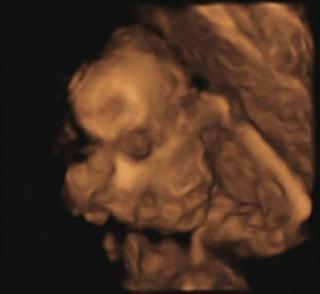

nas chrobacik.. nostek sa do 3d nevmestil, lebo sa nim mame tlaci o maternicu.. 😅